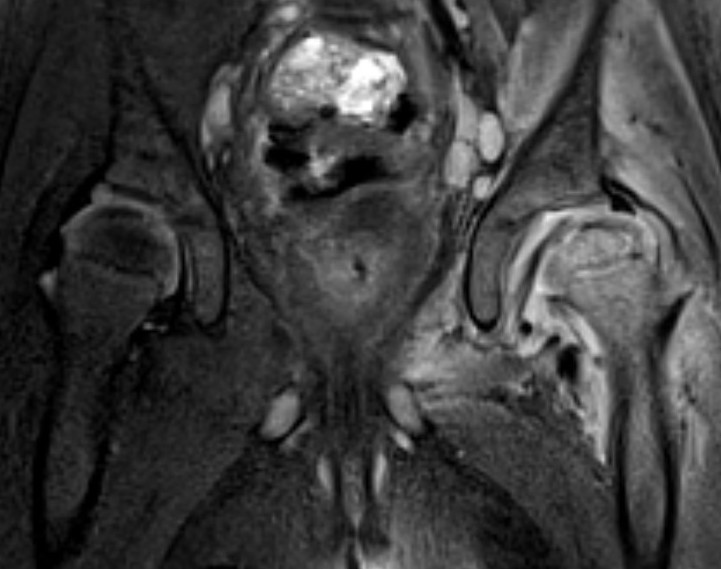

Hip OMHip OM

Subluxation of the hip joint with effusion and bone marrow changes

Proximal femoral osteomyelitis

Bone marrow edema and osteomyelitis in the femoral head